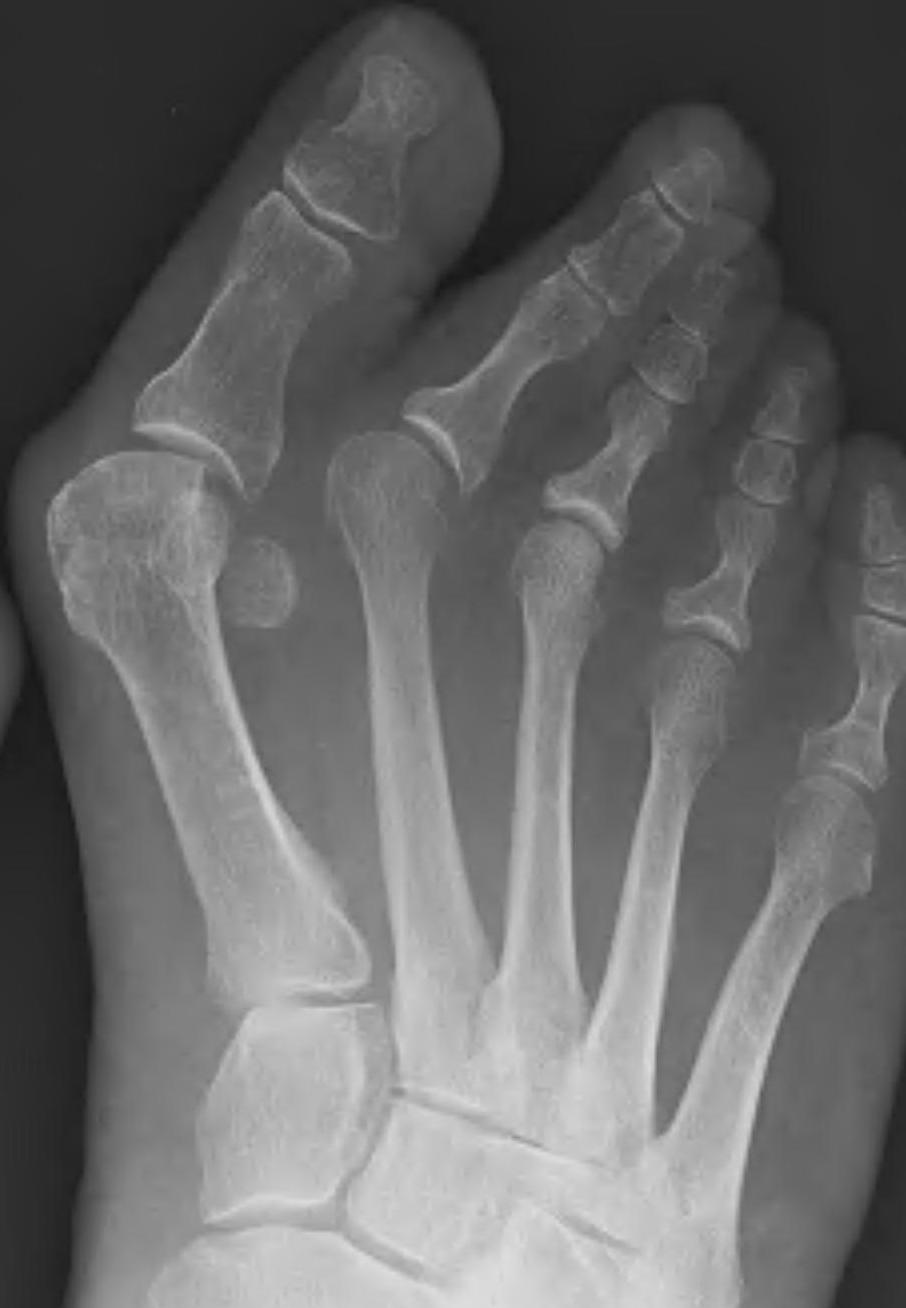

Scarf osteotomy + DSTP

Indications

- moderate hallux valgus

Technique

Dorsomedial approach

- distal soft tissue release

- medial eminence resection

- preserve blood supply at plantar aspect of the metatarsal neck

Longitudinal cut

- oblique: plantar proximal / dorsal distally

- leave strong plantar portion of head to prevent dorsiflexion

Transverse cuts

- plantar proximal / dorsal distal

- angle of 45o with the long cut

Translation

- plantar fragment medially

- can rotate to reduce pronation

Fixation with screws